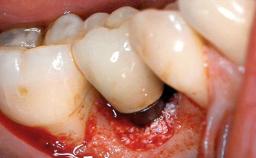

This case describes the ongoing management of a 64-year-old healthy, non-smoking female patient with erosive oral lichen planus (OLP) affecting the gingivae and the buccal and lingual mucosa. The peri-implant mucosa was also affected subsequent to implant placement. The patient had osseointegrated implants (four in the maxilla, four in the mandible) placed following extraction of hopeless teeth and a healing period. The patient had a history of OLP prior to implant placement and had been referred to an oral-medicine specialist for definitive diagnosis and treatment. She exhibited generalized oral mucosal involvement. Following a clinical assessment, biopsy, and blood tests, she was treated with topical corticosteroids. Systemic prednisolone was reserved for severe flare-ups. Amphotericin lozenges were used in combination with corticosteroid treatment to prevent the development of oral candidiasis.